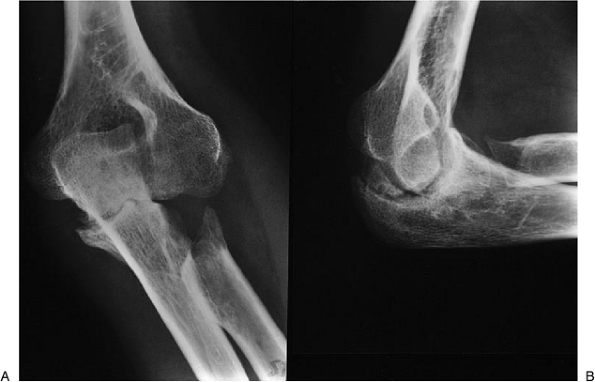

following surgery and, as shown here, 2 years later has range of elbow

motion of from 15 to 115 degrees with full pronation and supination (Fig. 22-26).

Medial/lateral stability was excellent, with 15 degrees of deviation on

stress testing. He has been followed at intervals and has recently

retired from his work at age 61; a recent radiograph 18 years after

surgery shows preservation of excellent flexion and extension (Fig. 22-27).

![]() |

Figure 22-26. A: After surgery the patient has an arc of motion of 15 to 115 degrees. B: Normal pronation and supination.

Figure 22-27. A,B: Radiographs 18 years after surgery show preservation of excellent joint surface, and the patient is pleased with the result.